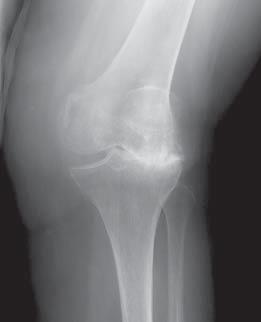

¿Qué es un reemplazo de rodilla?

Un reemplazo de rodilla es en realidad un reemplazo de hueso y cartílago utilizando una superficie artificial. No se extrae toda la rodilla, como algunas personas piensan. En su lugar, los extremos dañados de los huesos se recubren con un implante: una aleación de metal en el fémur y un espaciador de plástico duradero en la tibia y la rótula. Esto crea una almohadilla suave nueva y una articulación funcional que puede reducir o incluso eliminar el dolor, lo que permite una mejor movilidad y calidad de vida.